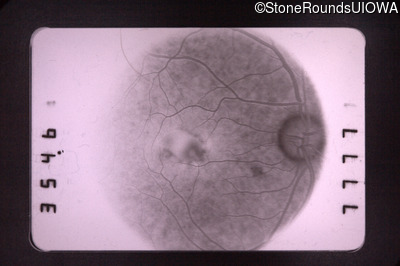

Visit at age: 47 years

Fundus Photography - Left - 20/30 +1